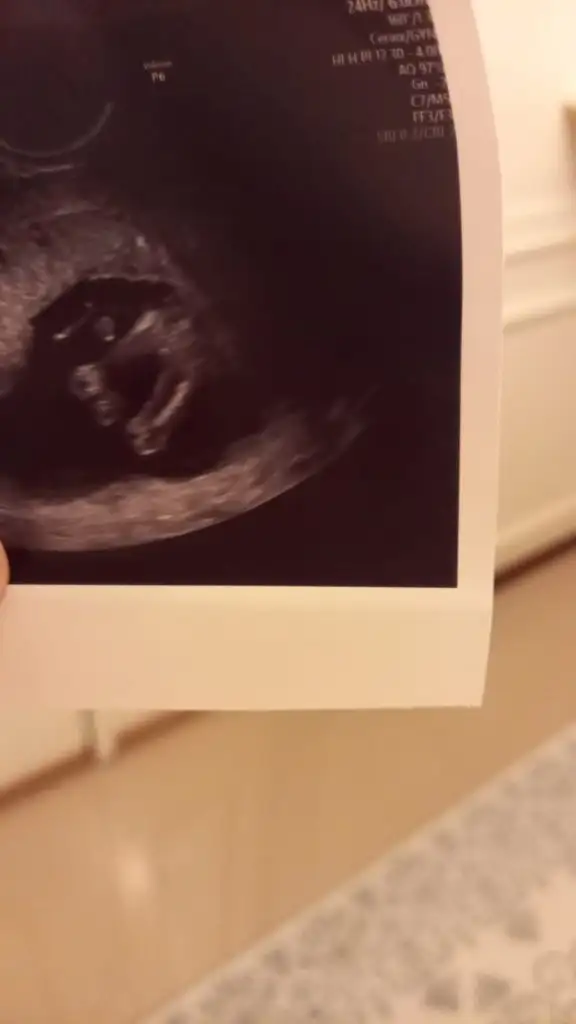

Öncelikle bebişi gördüm sata göre 12+4 ultrasonda da 12+6 çıktı maşallah elleri ayakları yüzü herşeyi belliydi. Lakin kadın inadına belden aşağısına tutmadı. Dedim bi tahmin yapsanız şimdi yanıltır dedi. Hatta yüzü falan çok narin kız heralde dedim belli olmaz dedi. Ultrason güzeldi renkli de çok belli olmuyo da siyah beyazda parmakları bile belliydi görsem ben bile anlardım ama bırakın bacak arasını aşağılara bile bakmadı. Ense ölçüsü falan alsın diye hep kafa kısmıyla ilgilendi bebiş hareketliydi arkasını önünü döndü sırt üstü yattı falan ama ısrarla üste tuttuğu için hiçbişe görmedim. Bütün bir foto bile vermedi ki en azından nub bakalım çok sinir oldum. Bir de elim dolu gittim bişeyler götürdüm hediye😒

Durum bu kızlar bebişim iyi çok şükür bir ara bacak arasını dolu gibi gördüm ama sadece önü dönükken ve saniyelik gördüm asla anlamadım yüzü falan kız gibiydi yuvarlaktı hatları. Ne olursa olsun hiç önemli değil ama ultrasonu iyi olduğu halde tahmin bile yapmaması canımı sıktı ve asla özeline gidip artı paralar dökmeye değmez. Eşim erkek dr a karşı tavırlıydı alttan bakılıyo diye ama artık karından bakılıyo eli de mecbur kaldı😂 Bir de bu kez eşimi de soktu içeri eşim de gördü artık ne kadar anladıysa video çekebilir miyiz ablaları görsün dedik hayır dedi😒 Renklinin ekrandan foto çektirdi siyah beyazda da el sallar gibi sadece kafası ve kolu var fotoda. Ense kalınlığı 1.6 dedi burun kemiği de vardı kıpır kıpırdı dr bastırdıkça o itti sağlıklı görünüyordu buna şükür❤️

Herkese merhaba gebeliğimin 13. haftasındayım yazılarınızı sürekli okuyrorum ama ılk defa yazıyorum:) doktorumuz kıza benzettı ancak bacak arasında sıslık gordu bekleyın dedı basına gelen var mı acabaEki Görüntüle 2992438